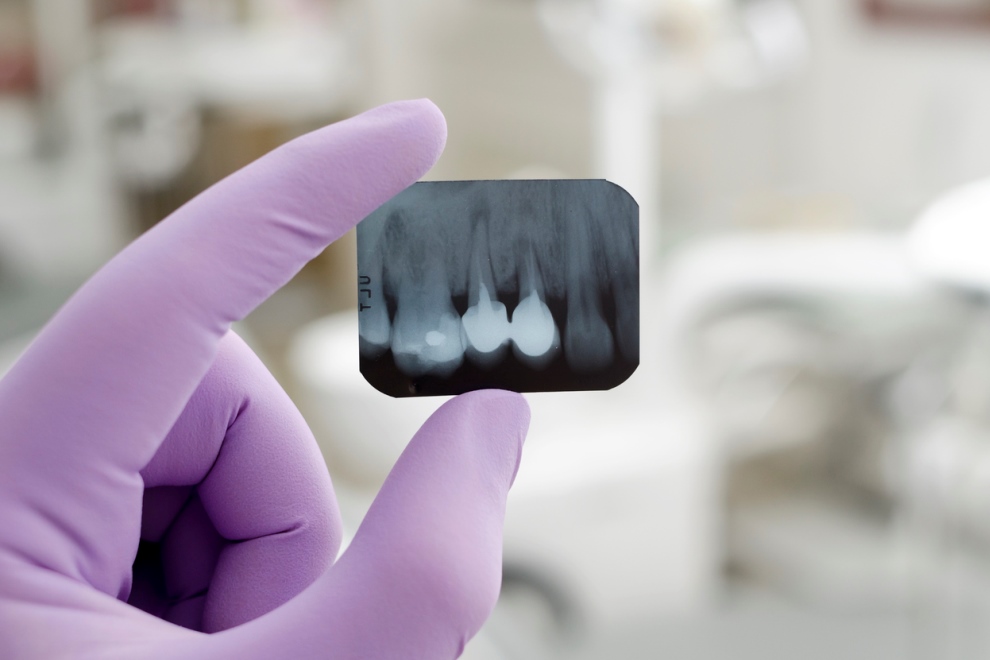

RADIOGRAFIA PERIAPICAL RAYOS X

Contamos con radiografías periapicales las cuales garantizan un diagnostico sertero y eficaz permitiendo elegir el tratamiento adecuado así como el control y avance y evaluación de los procedimientos. Son una herramienta importante para ayudar al dentista a diagnosticar adecuadamente las necesidades de su salud oral. Estas le permiten al dentista determinar si usted tiene caries dentales (cavidades), enfermedades periodontales (encías), abscesos o crecimientos anormales, tales como tumores o quistes. También muestran la ubicación y condición de los dientes impactados o los dientes que no han brotado.